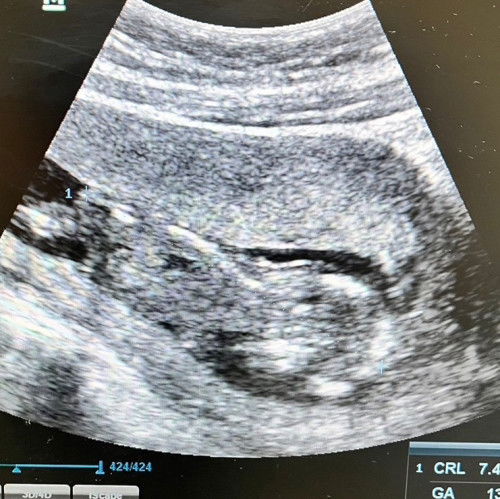

ดูเหมือนน้ำคร่ำน้อยไหมคะ

สอบถามแม่ๆหน่อยค่ะ จากภาพดูเหมือนมีน้ำคร่ำน้อยมั้ยคะ อันตาซาวด์ก็ไม่ได้ถามคุณหมอ 13w4d #ท้องแรกคะ #ขอบคุญคำตอบล่วงหน้านะคะ